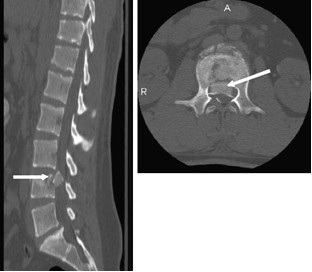

Poniżej przedstawiono obraz CT w przekroju strzałkowym oraz aksjalny odcinka lędźwiowego kręgosłupa z widocznym złamaniem „wybuchowym” trzonu L4, przemieszczeniem fragmentu kostnego w obręb kanału kręgowego (strzałka),z uciskiem worka oponowego i korzeni ogona końskiego. Wskaż właściwe zasady leczenia tego typu urazu w zależności od prezentowanych przez pacjenta objawów uszkodzeń neurologicznych:

1) jedynym leczeniem z wyboru, jeżeli obserwujemy częściowe uszkodzenie funkcji neurologicznych jest rozpoczęcie wlewu metylprednizolonu do 8 godz. od urazu, leczenie operacyjne odroczone;

2) interwencja chirurgiczna polegająca na dekompresji i stabilizacji powinna być wykonana w trybie pilnym jeśli obserwowany zespół ogona końskiego ma charakter dynamicznie narastającego uszkodzenia częściowego;

3) rozpoznanie tego typu zmian pourazowych nie wymaga podjęcia wczesnego leczenia, wskazane jest jedynie postępowanie zachowawcze stabilizujące ogólny stan chorego, a wszelkie działania chirurgiczne mogą być odroczone;

4) w przypadku uszkodzenia całkowitego leczenie operacyjne do 24 godz., celem jest skrócenie czasu hospitalizacji, ułatwienie rehabilitacji, poprawa stabilności kręgosłupa i zapobieganie deformacjom;

5) interwencja chirurgiczna polegająca na dekompresji i stabilizacji powinna być wykonana do 3 dni następujących po urazie jeśli obserwowany zespół ogona końskiego ma charakter uszkodzenia częściowego i jest stabilny.